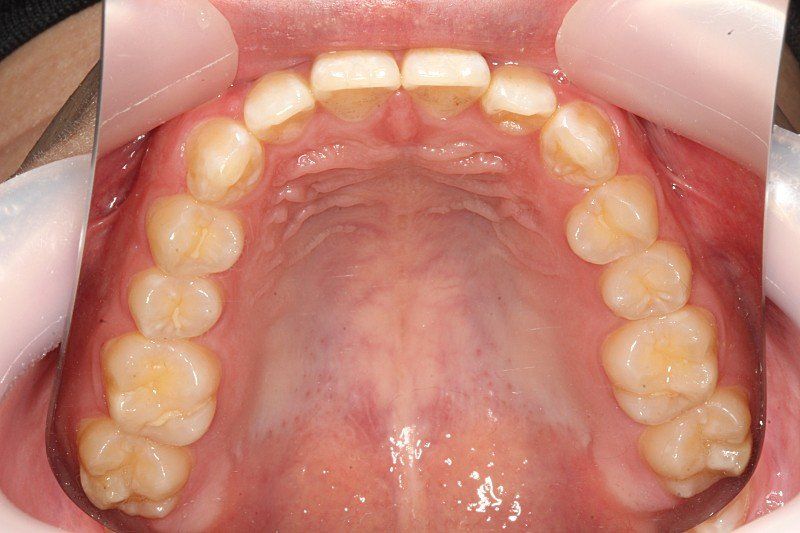

약간 비대칭이 있긴한데... 치아중심선 맞추기랑 앞니 부분적으로 절단교합이 있어서 교정할려고 해요

인비절라인으로 하면 1년 정도면 된다고 하는데 투명교정 하게되면 치아중심선이랑 12번치아 앞니 교합 교정, 전체적 치아가 살짝 틀어진거 교정 효과 볼 수 있을까요?

• 4번 째 사진